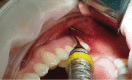

Gingival recession is an oral health problem that affects a large part of the population. Several treatments are suggested in the current literature; among them is the use of buccal fat pad grafting. The objective of this case report is to describe the treatment of a Miller Class I gingival recession using a nonpedicled buccal fat pad graft immediately after performing the surgery for buccal fat pad removal (bichectomy technique). First, bilateral surgical removal of the buccal fat pad was performed with the main objective of eliminating oral mucosa biting. The recipient site was prepared to receive a portion of the fat pad that was cut and macerated in a size that was sufficient to cover the recession. The patient was followed up at 15, 30, 60, and 365 days postsurgery, and the results showed an elimination of the oral mucosa biting and complete coverage of the gingival recession. It was concluded that the nonpedicled buccal fat pad graft is another option for the treatment of Miller Class I recessions.